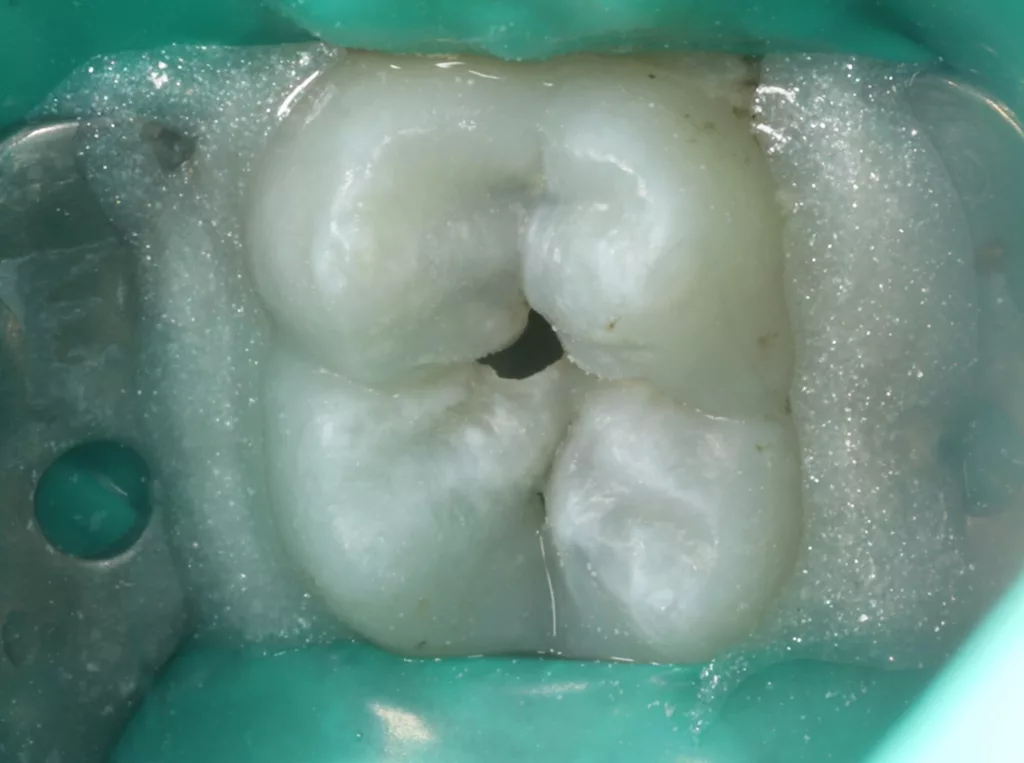

Unter Lokalanästhesie mit dem STA-System (Milestone Scientific, USA) und Septanest 1/200 000 (Septodont, Frankreich) wurde die überstehende Gingiva mit dem Khors Koagulator (Эctatex, Ukraine) koaguliert und der Bereich unter Kofferdam kontaminationsfrei dargestellt (Klammer U67, KSK Dentech, Japan). Die schmalen Fissuren wurden mit dem Fissurenbohrer CD-53F (Mani, Japan) erweitert, um anschließend mittels RONDOflex plus 360 (KaVo Dental, Deutschland) und Pulver 27 µm vollständig gereinigt werden zu können. Es konnte weder durch visuelle Inspektion noch Sondierung mit 0.08 H-file (Mani, Japan) ein Defekt des Zahnschmelzes festgestellt werden. Unter Berücksichtigung der Integrität des Zahnschmelzes, der Symptomlosigkeit, des Behandlungszeitpunktes, Alters des Kindes und Wachstums der Zahnwurzeln fiel gemeinsam mit den Eltern die Wahl auf eine konservative Therapie. Es wurde eine Fissurenversiegelung mit Clinpro Sealant (3M, USA) unter Anwendung eines adhäsiven Behandlungsprotokolls mit Optibond FL (Kerr, USA) durchgeführt. Dieser klinische Fall ist dahingehend einzigartig, da alle anderen ersten und zweiten Molaren des Kindes ebenso von einer PEIR betroffen waren (Grad 1 bis 2 der Läsion nach Seow) (Abb. 3 und 12). Normallerweise ist nur ein Zahn bei einer Patientin oder einem Patienten betroffen. Die Zahnkronen der anderen betroffenen Zähne erwiesen sich bei der klinischen Untersuchung als intakt; die radioluzenten Läsionen innerhalb des koronalen Dentingewebes waren wesentlich kleiner als die von Zahn 36. Daher wurde auch bei diesen Molaren das gleiche Behandlungsprotokoll angewendet und nur eine Fissurenversiegelung durchgeführt.

Das siebenjährige Mädchen wurde von einer Kollegin zur Behandlung einer atypischen intrakoronalen Aufhellung im Kronenbereich des nach Durchbruch befindlichen symptomatischen Zahnes 46 überwiesen (Abb. 20). Anamnestisch bestanden seit zwei Tagen kurzintervallige Spontan- und Nachtschmerzen, die mit Ibuprofen 40 mg/ml Kindersirup behandelt wurden. Das Röntgenbild zeigte einen umfangreichen runden Dentindefekt unter intaktem Zahnschmelz, der bis in das Pulpakavum reichte. Daraus ergab sich die Verdachtsdiagnose PEIR des Zahnes 46 (Grad 3 der Läsion nach Seow) in Kombination mit einer akuten Pulpitis. Nach Leitungsanästhesie am Foramen mandibulae mit Septanest 1/100 000 (Septodont, Frankreich) und STA-System (Milstone Scientific, USA) konnte der Zahn mithilfe von Kofferdam (Klammer U67, KSK Dentech, Japan) gut isoliert werden (Abb. 21). Um die ursprüngliche Zahnanatomie zu imitieren, wurde ein Okklusalstempel aus dem flüssigen Kofferdam OpalDam (Ultradent, Frankreich) und einem Microbrushapplikator angefertigt.

Der PEIR-Defekt schimmerte unter der lingualen Querfissur deutlich dunkler durch (Abb. 21), sodass die Entscheidung getroffen wurde, den Defekt an genau dieser Stelle zu eröffnen (Abb. 22). Das resorbierte intrakoronale Weichgewebe, das die Läsion nur zum Teil füllte, konnte dann gut visualisiert werden (Abb. 22). Kariös verändertes Dentin wurde nicht gefunden. Nach Eröffnung des Pulpahorns sah die Pulpa blass und avaskulär mit Anzeichen einer geringen Blutung aus (Abb. 23). Die komplette Kronenpulpa wurde bis zur Höhe der Kanaleingänge mit einem runden Diamantbohrer unter Wasserkühlung entfernt. Vor und nach der Prozedur wurde die Läsion zuerst mit 1%igem NaOCl und anschließend mit physiologischer Kochsalzlösung gespült. Die Blutung stoppte innerhalb von zwei Minuten vollständig, die Wurzelpulpa erschien gesund, regulär vaskularisiert und sauber (Abb. 24). Es wurde eine reversible Pulpitis diagnostiziert. Die Abdeckung der Wurzelpulpa erfolgte mit einem hydraulischen Kalziumsilikatzement (Rootdent, Technodent), der mit dem Glasionomerzement Fuji II LC (GC, Japan) als temporäre Füllung abgedeckt wurde. Die Platzierung des MTA-Zements wurde abschließend mittels einer Röntgenaufnahme überprüft (Abb. 27). Nach zwei Wochen war die junge Patientin komplett beschwerdefrei. Unter erneuter Trockenlegung mit Kofferdam wurde die adhäsive koronale Restauration mit Komposit Estelite ASTERIA OCE, A2B und Universal Flow AO2 (Tokuyama, Japan) mithilfe eines vorab angefertigten Okklusalstempels erstellt (Abb. 25 und 26). Ein Jahr später kam die Patientin beschwerdefrei zur Nachkontrolle. Das Röntgenbild (Abb. 28) zeigte keinen pathologischen Befund sowie eine physiologische Weiterentwicklung des Wurzelwachstums in Länge und Dicke der Wurzelwände.